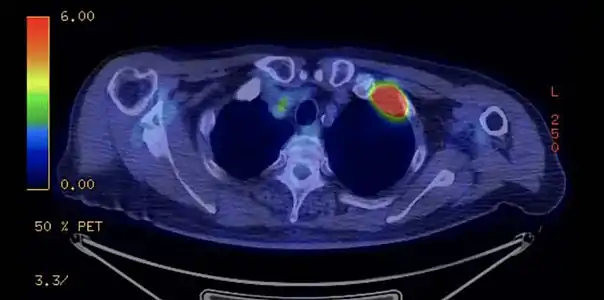

PET-scanner du même patient[14]. PET-scanner du même patient[14].

Dans le cadre du bilan d'extension, le TEP scanner aide à rechercher les localisations secondaires métastatiques et à préciser l'envahissement ganglionnaire.